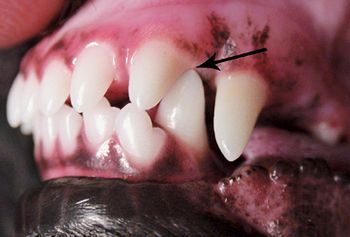

Canines' canines are often unaffected, but be on the lookout for this condition in other dentition.

Tips for catching this invasive neoplasia as early as possible.

Correct management of periodontal patients in veterinary practice demands a thorough understanding of veterinary dental radiographic anatomy, periodontal probing and many times open evaluation and direct visualization of diseased areas. Stage III periodontal disease in particular requires advanced skills and familiarization with periodontal pathophysiology to make decisions to attempt to grow new supportive tissue adjacent to compromised teeth or extract them.